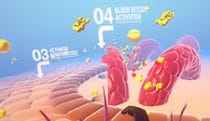

A multifaceted approach to MM

Look & feel explorations -

Early-stage atherosclerosis

Work -

Journey into the body MOA

Work -